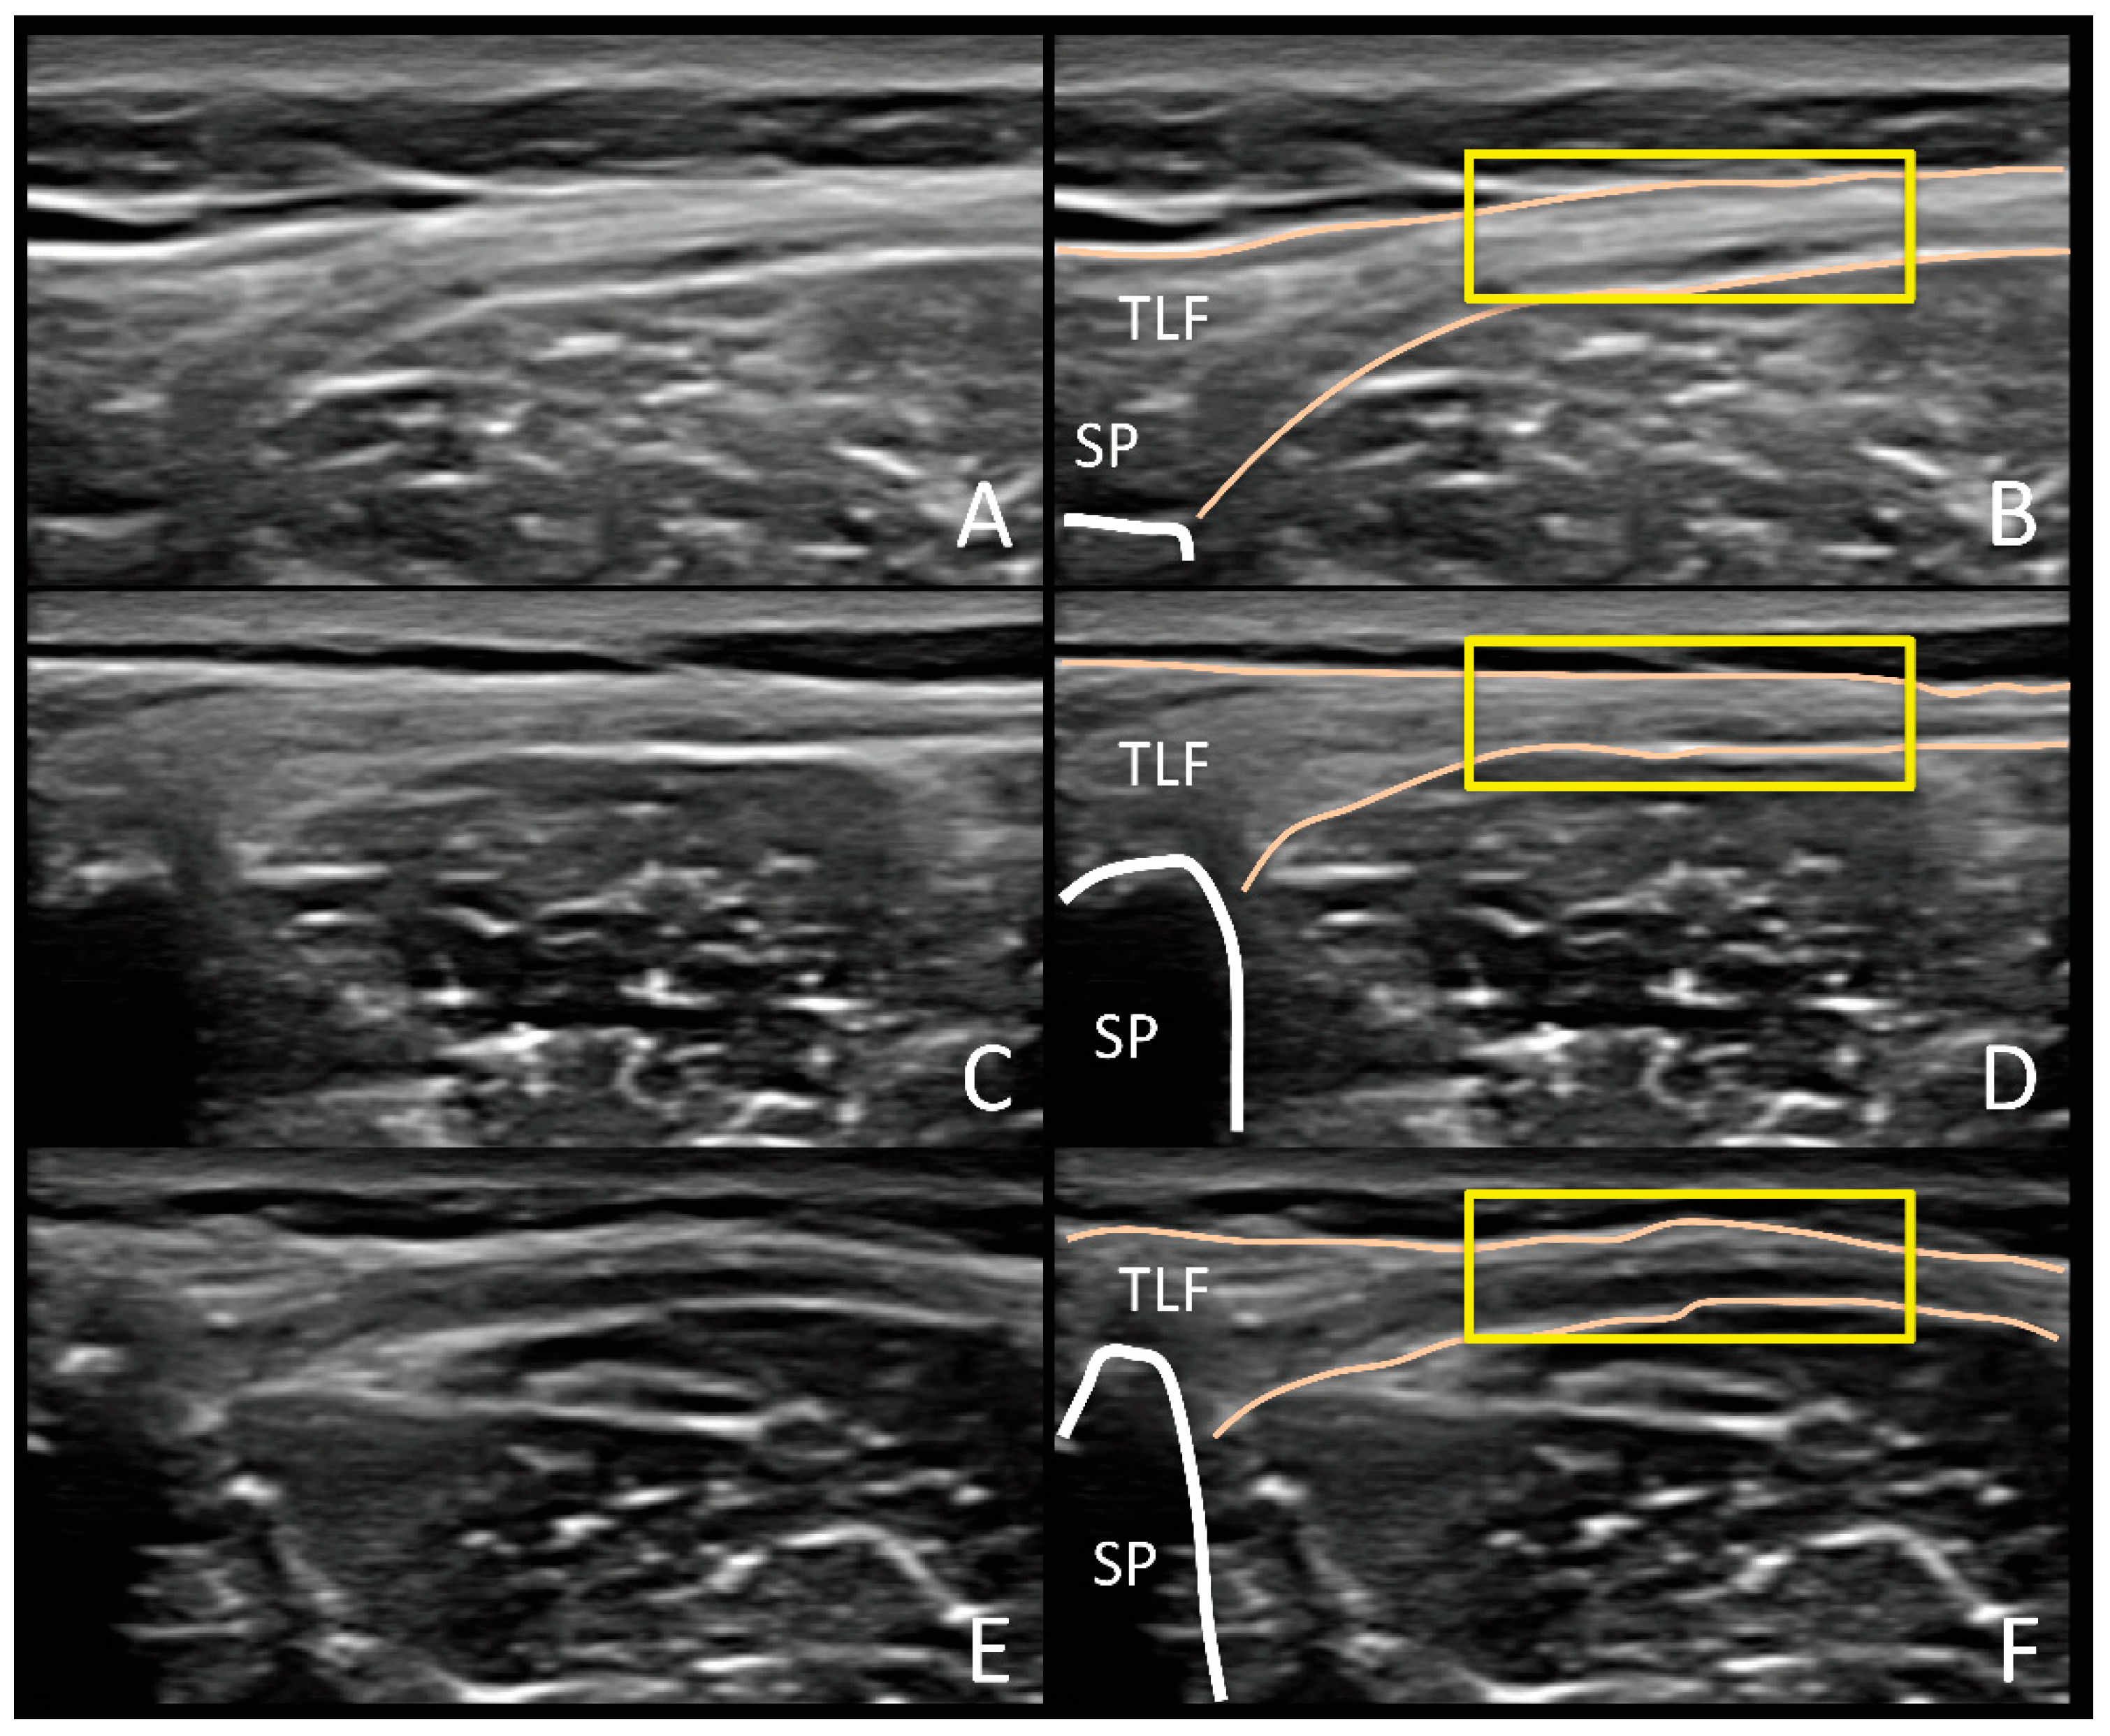

| 5. TLF-TH measurements |

| 6. Categorization of TLF-MPH into 4 groups based on the Likert-type scale |